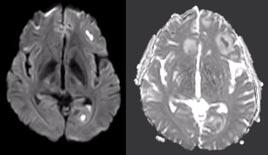

antimicrobiële therapie gestart, te weten amoxicilline en ceftriaxon iv in hoge dosis. De diagnose werd bevestigd door liquordiagnostiek die middels kweek een Klebsiella pneumoniae als verwekker aantoonde. Middels whole genome sequencing (WGS) bij het RIVM werd vastgesteld dat het om MLST type 23 ging welke bekend staat als de ‘hypervirulente Klebsiella pneumoniae (hvKp). Deze was gevoelig voor alle geteste antibiotica, met uitzondering van amoxicilline (resistent). Uit aanvullend onderzoek met MRI-cerebrum bleek er sprake te zijn van multipele cerebrale abcessen (figuur 1 en 2). Bijkomend op PET-CT werden pulmonale abcessen, een leverabces en sterk verhoogde activiteit in de prostaat gezien. Echografisch werd een abces van de prostaat uitgesloten. Het leverabces kon niet volledig worden gedraineerd, maar de kweek het punctaat toonde dezelfde verwekker. Een cardiale strooihaard werd middels een echo cor uitgesloten. Mogelijk is een prostatitis de primaire infectiebron van K. pneumoniae geweest.

Figuur 1.

3DT1 HR gradiënt sequentie na intraveneuze toediening van gadolinium toont een tweetal ringvormig contrast aankleurende lesies met centrale non-enhancement van respectievelijk 1,4 cm links frontaal en 1,0 cm links occipitaal. Let ook op de aankleuring langs het ventrikelependym links occipitaal.

Figuur 2.

DWI sequentie B1000 toont uitgesproken diffusierestrictie in de respectievelijke laesies links frontaal en links occipitaal als ook in de zijventrikel-occipitaalhoorn links. Dit bevestigt de diagnose hersenabcessen met daarnaast meningitis/ventriculitis in de linker zijventrikel.

Voor de diagnostiek naar cerebrale abcessen is een MRI met diffusie en post-gadolinium opnames essentieel. De laesies vertonen diffusierestrictie, dat wil zeggen een hoog signaal op de DWIopnames met corresponderend laag signaal op de ADC-opnames. Diffusierestrictie is indicatief voor pus. Watermoleculen kunnen in het ingedikte materiaal (pus) niet vrij diffunderen over semipermeabele barrières van bijvoorbeeld extracellulair naar intracellulair, maar blijven binnen het verdikte abceskapsel. Na gadolinium wordt er (scherpbegrensde) randaankleuring gezien van alle cerebrale abcessen.